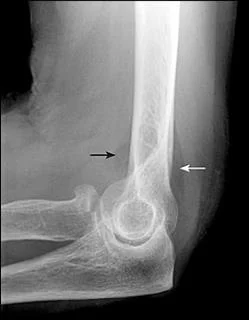

Fracture Distal Humerus

- Treated by open anatomical reduction and internal fixation by plates and screws

- Early mobilization to prevent elbow stiffness